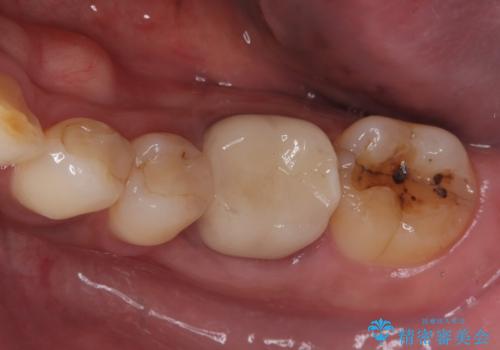

銀歯がとれた セラミックインレーで修復

- 銀歯が取れたとのことで来院されました。

拡大鏡下で丁寧に虫歯を取り除き、セラミックインレーによる修復治療を行いました。

銀歯を固着するセメントは経年劣化し溶け、隙間ができます。そこにプラークが侵入して虫歯が再発します。今回のように銀歯が脱離してしまうこともあります。

今回は銀歯が取れたので、虫歯が神経まで達して痛みが出る前に、強度・審美に優れ、虫歯の再発の少ないセラミックインレーにて治療を行うことができました。